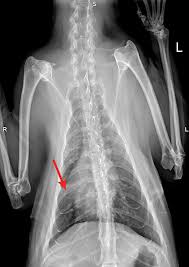

Signs Of Lung Cancer In Cats : Thoracic Tumors Lung Dr Julius Liptak - Symptoms of feline lymphoma cancer according to dr.. Other common symptoms of lymphoma in cats include swollen lymph nodes, loss of appetite, weight loss, and difficulty breathing. This can occur because of spread of tumor to the bones of the limbs (more common in cats), or due to a secondary effect that the tumor has on bone growth (more common in dogs). Arteaga, these are the symptoms of lymphoma in cats: Lymphoma and lymphosarcoma is common among cats with felv infections. Adenocarcinoma (papillary or bronchioalveolar) is the.

A severe acute attack is likely to result in a cat's death if veterinary treatment is not immediately available. That's the thing about cancer in cats. Externally we can see lumps and bumps. In fact, cancer accounts for almost half of the deaths of pets over 10 years of age. Panting, abdominal effort when breathing, wheezing, coughing, and inability to exercise are also signs of lung tumours in cats. Lymphoma and lymphosarcoma is common among cats with felv infections. These signs often include decreased appetite, weight loss, increased thirst, and vomiting. This combined with the fact that cats tend to hide illness well means that when we find cancer in cats it's often both serious and advanced. Cats with lymphoma may have an increased or decreased appetite, or you may notice no change in appetite. Radiation also works for localized tumors, particularly tissue that can't be surgically removed. This can occur because of spread of tumor to the bones of the limbs (more common in cats), or due to a secondary effect that the tumor has on bone growth (more common in dogs). Arteaga, these are the symptoms of lymphoma in cats: Occasionally dogs and cats with lung cancer are lame.

Cancers Tumors In Cats Hill S Pet from www.hillspet.com Panting, abdominal effort when breathing, wheezing, coughing, and inability to exercise are also signs of lung tumours in cats. These signs often include decreased appetite, weight loss, increased thirst, and vomiting. Respiratory, nasal or pulmonary carcinoma is most common in the muzzle and lung cancer in cats. Bad breath may indicate oral cancer, although it's also a symptom of a sinus infection. This can occur because of spread of tumor to the bones of the limbs (more common in cats), or due to a secondary effect that the tumor has on bone growth (more common in dogs). It causes difficulty breathing, snorting, sneezing, coughing and nasal secretions. Up to 25 percent of pets with lung cancer may not show any clinical signs of illness. Learn more about pneumonia in cats.

In cats with renal lymphoma, signs associated with kidney failure may be seen. Difficulty in breathing can be a sign,. This can occur because of spread of tumor to the bones of the limbs (more common in cats), or due to a secondary effect that the tumor has on bone growth (more common in dogs). Terminal respiratory secretions (saliva and bronchial secretions) can build up in the back of the cat's throat as the coughing and swallowing reflexes decline, which can cause a gurgling or rattling sound, known as the death rattle Cancer may be localized, or it may invade adjacent tissue and spread throughout the body. Although cancer may be one of the potential causes of a variety of different signs (especially in older cats), it is important to remember that many other diseases commonly cause the same signs as cancer and that, even where cancer is diagnosed, there may well be treatment options that will enable control or management of the disease, at least. Very few mammary gland growths in cats are benign—85 to 90 percent are malignant and spread to lymph nodes, lungs and the chest cavity. Lung cancer (pulmonary neoplasia) is a malignant tumour of the lungs that can be primary (originating in the lungs), or secondary (having originated elsewhere and spread to the lungs). Other symptoms of lung cancer include: Only about two thirds of dogs and cats actually exhibit clinical signs. The signs indicating a primary lung tumor can vary, depending on the location of the tumor, speed of tumor growth, and presence of previous or current lung disease. Chemotherapy is an option for the cat that has cancer in multiple areas of the body. The cat will have a dry cough and will be less active.

Cancer In Cats Elwood Vet from images.squarespace-cdn.com However, there are many different type of cancer, and cats can get other cancers, even very rare ones. For example, certain breathing problems and coughing are surprisingly uncommon; Symptoms of feline lymphoma cancer according to dr. Vomiting and diarrhea are common signs of gastrointestinal lymphoma. Less than a third of cats diagnosed with lung cancer have breathing problems. The signs indicating a primary lung tumor can vary, depending on the location of the tumor, speed of tumor growth, and presence of previous or current lung disease. If the cancer originates in other parts of the body, the coughing will not be present in the initial stages of the disease. This type of cancer is rare in cats, and accounts for less than 1% of all tumours.